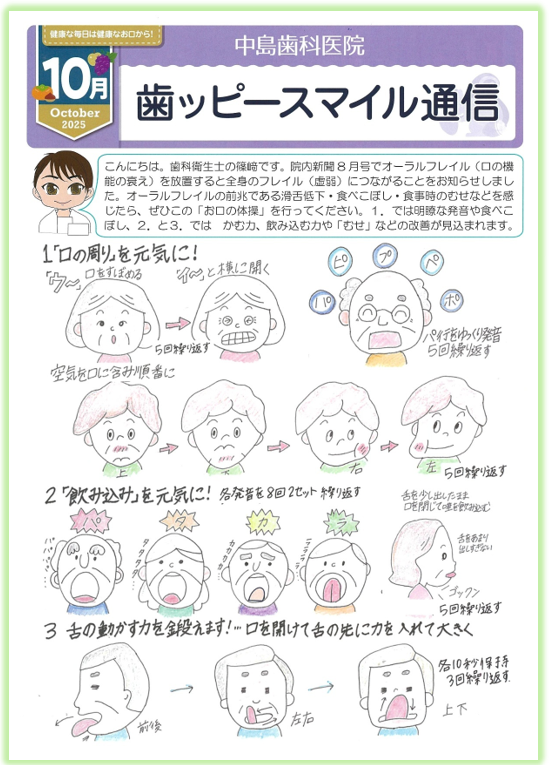

・2025年10月号 院内新聞

10月号は歯科衛生士の篠﨑が担当しました。 オーラルフレイルの予防や、改善のために、気軽に行える口腔体操を紹介しています。